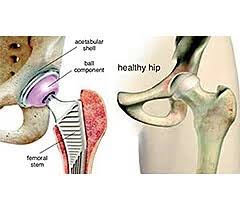

Introduction Hip pain can severely impact daily life, making simple …

Introduction Persistent hip pain can severely limit daily activities such …

Introduction Hip pain can significantly affect your daily life, making …